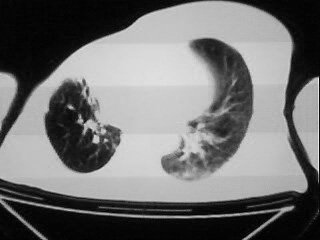

以下是引用随光逐影在2009-2-10 0:07:00的发言:[br]1)右肺放射性肺炎并节段性肺不张?请结合相关病史。2)右侧胸膜肥厚、粘连。3)心包膜增厚(或心包少量积液)。